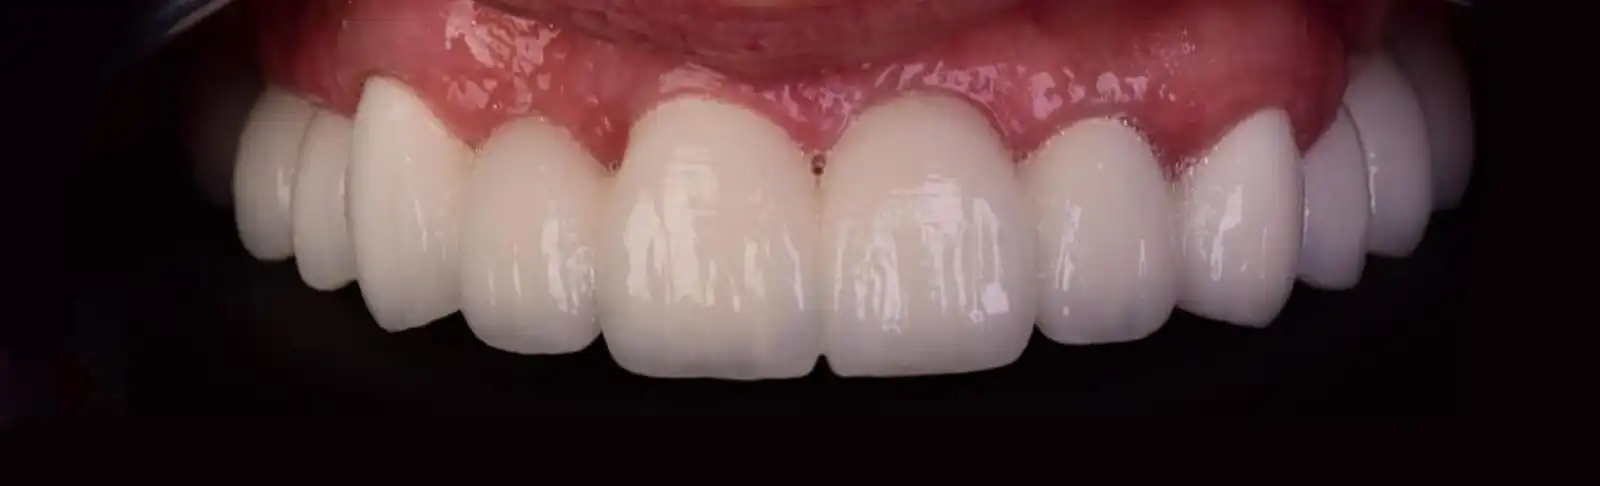

3. Finalizarea lucrării

După 3/6 luni de la inserarea implantului se va primi lucrarea finală pe implant. Lucrarea recomandată este să fie o coroană înșurubată din zirconiu metalo ceramică sau metalo compozit injectat.

Calitatea implantului dentar și materialul din care este confecționată lucrarea protetică sunt esențiale pentru durabilitatea unui tratament pe termen lung.